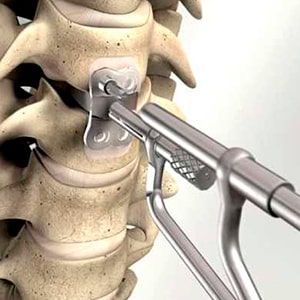

- артродез – хирургическая процедура при переломе позвоночника, включающая установку металлических конструкций для выравнивания и поддержки позвоночного столба;

- операция по замене позвонка или межпозвоночного диска на искусственный или биологический протез.

Малоинвазивные операции на позвоночнике

Операции выполняются через небольшие разрезы или естественные отверстия:

- Лазерная вапоризация. Этот метод используется при небольших грыжах хрящевой ткани (до 6 мм). Лазерное воздействие снижает давление деформированного хряща на соседние нервные окончания, что помогает устранить болевые ощущения.

- Пункционная вертебропластика. Этот процесс включает в себя укрепление костной или хрящевой ткани позвонка путем введения в межпозвоночные отверстия специального цементирующего состава на основе акриловых смол.

- Нуклеопластика. Восстановление структуры межпозвонкового диска осуществляется с помощью электрода, который воздействует на поврежденную область хрящевой ткани.

- Эпидуроскопия. Это эндоскопическое обследование, проводимое с использованием оптического прибора, с целью диагностики.

Важно! Малоинвазивные методы характеризуются высокой безопасностью, эффективностью (более 80%) и отсутствием длительного периода восстановления после операции.